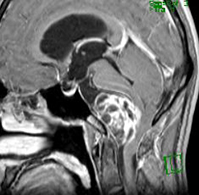

症例1) 65歳男性、頭蓋底部巨大髄膜腫、外科手術のみ

<画像所見>

巨大脳腫瘍を認める。

錐体斜台部巨大髄膜腫を認め、

神経や血管を巻き込んでいる。